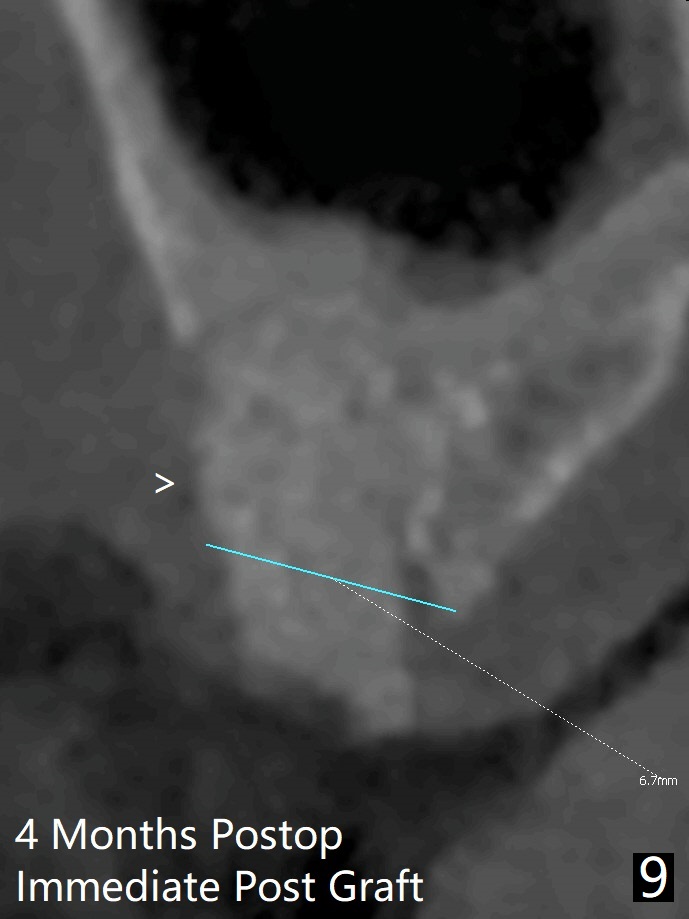

使用来自钻头的自体骨做提升,植体植入后,颊侧骨板薄,刚好骨下。使用5.5毫米profile drill后,放置愈合基台,术后三个月脱落,他再次要求修复,甚至提出退款,不愿意回诊所,因为他有糖尿病,新冠病毒高危人群。 放置小号愈合基台(图二)。他原来托牙是Valplast,没有occlusal rests,不能经过修改临时使用,可能将直接放置修复基台做临时牙冠。放置修复基台后(图三(术后三个月)),制作临时牙冠时,发现前者有些松动,后者就没有粘固。当基台完全就位,它最冠方与植体没有间隙(箭头),根方有间隙(空心箭头)。其实愈合基台也是一样(图一,二)。后来植体松动(术后4个月),拔除,植骨(图四),颊侧骨板缺失(图五:B)。植骨后5个月2号牙疼痛需要拔除种植(图七),与3号牙一起种植(图六),颊侧骨板修复,但是高度有所下降(箭头)。The narrow ridge with the intact buccal plate (Fig.8 >) can hold a 4x8.5 mm implant. The buccal plate is lost 4 months postop (Fig.9) and restores 5 months post graft (Fig.10). Return to Upper Molar Immediate Implant, No Deviation Coronal and Apical Gap in IBS implant Protect Graft Xin Wei, DDS, PhD, MS 1st edition 06/22/2020, last revision 05/02/2021